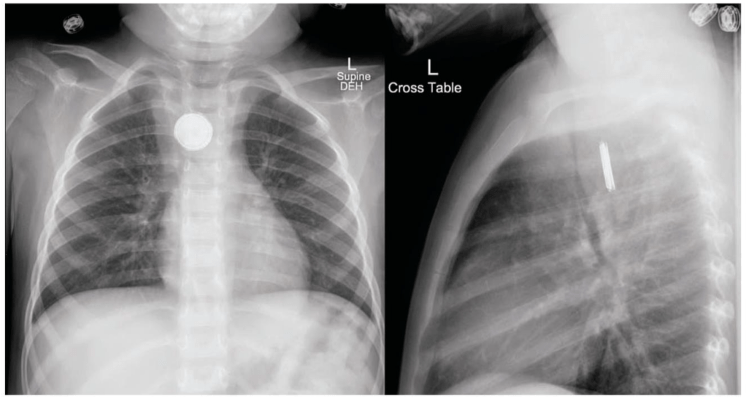

Button Battery Ingestions Gepost op 1 oktober 2018 door netwerkvsseh TOXCard: Button Battery Ingestions @emDocs.net Dit delen: Delen op X (Opent in een nieuw venster) X Share op Facebook (Opent in een nieuw venster) Facebook Delen op LinkedIn (Opent in een nieuw venster) LinkedIn E-mail een link naar een vriend (Opent in een nieuw venster) E-mail Afdrukken (Opent in een nieuw venster) Print Vind-ik-leuk Aan het laden... Gerelateerd